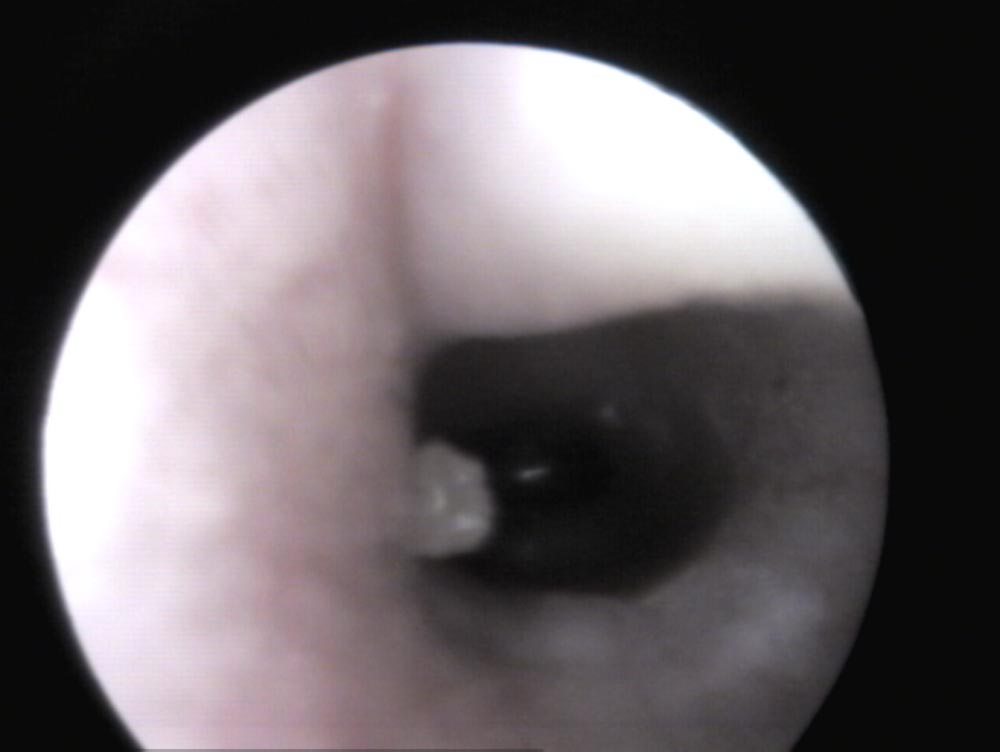

Der äußere Gehörgang wird mittels Otoskop/Videoendoskop untersucht. Bei einem gesunden Ohr kann man, durch leichten Zug der Pinna nach oben (Abb. 1), in der Regel bis zum Trommelfell sehen (Abb. 3). Ist Material im Ohrkanal vorhanden, gilt es zu unterscheiden, ob es „nur“ gestautes Zerumen (weiß in Tiefe, gelblich zur Öffnung hin) und der Gehörgang sonst reizlos ist, oder ob Entzündungszeichen (Rötung, Schwellung, Läsionen, Verflüssigung des Sekrets) (Abb. 4) und mögliche Primärursachen wie Fremdkörper und/oder Ektoparasiten vorhanden sind. Bei der Unterscheidung hilft die Zytologie.

Abb. 3: Blick auf das Trommelfell (Pars tensa – durchsichtig, Pars flacida – geweblich) eines Kaninchens

Bildquelle: J. Hein

Abb. 4: Blick in ein mit Eiter gefülltes Außenohr eines Kaninchens – das sonst reizlose Außenohr spricht für die Herkunft des Eiters aus dem Mittelohr